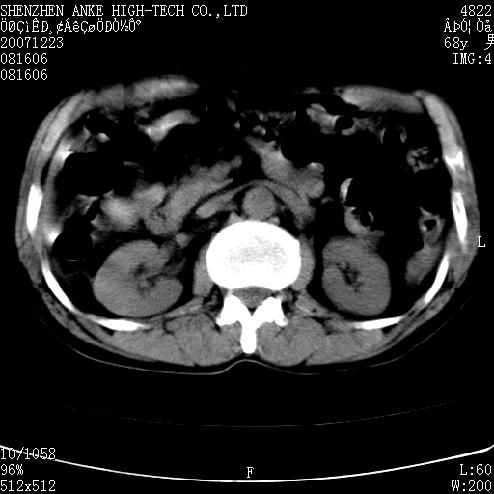

患者:男,63岁,2年前胆囊切除术后,现右上腹部剧烈疼痛近2天.

有无外伤史?右肾包膜下血肿可疑。

主要是问右肾有没有问题?患者无明显外伤史.

未见异常,病人差闭气,伪影较多.

肠管积气明显.

肠道准备不好,干扰影大。

肠道气体伪影干扰太大了,应该是干扰所致,未见明显异常。

肠道准备不好,胃底后壁显示不清,右肾改变考虑为伪影。

上腹部ct平扫未见明显异常。(肠道气体较多,患者呼吸了)

检查前最好叫病人喝些泛影葡胺,胃肠准备一下比较好